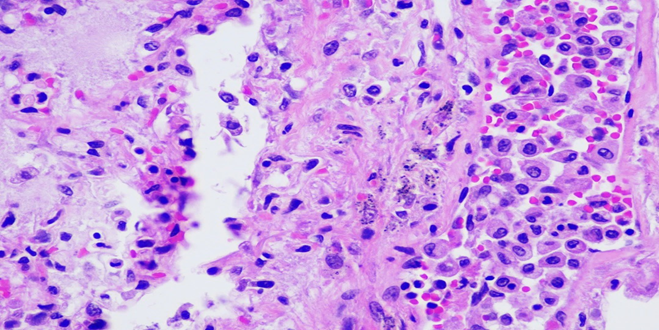

Figure 5A: Photomicrographs showing hemophagocytosis by macrophages in lymph node (H&E, 60X magnification).

Figure 5B: Photomicrographs showing hemophagocytosis by macrophages in bone marrow (H&E, 40X magnification).

Figure 5C: Photomicrographs showing hemophagocytosis by macrophages in spleen (H&E, 40X magnification).

Respiratory System: Sections of the right and left lungs show variable areas of vascular congestion, emphysematous changes, intraalveolar edema, and interstitial stromal acute and chronic and inflammation with focal interstitial fibrosis. Pleural fibrin adhesion and subpleural acute and chronic inflammation are identified. Clusters of intravascular histotypes identified, highlighted with CD68 and CD163. Granulomas, fungal forms, viral cytopathic effects, dysplasia, and malignancy are not seen. Special stains of GMS, GRAM, PAS and Iron support the findings. (Figures 4, 5A-C, 6A-D, 7A-C).